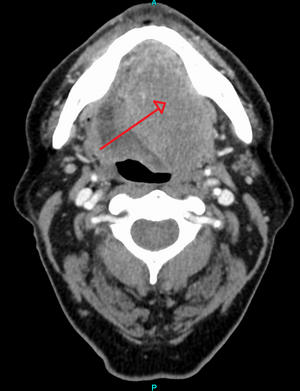

سرطان الرأس والعنق

حوالي 90%[4] من حالات سرطان الرأس والعنق (سرطان الفم، تجويف الأنف، البلعوم الأنفي، الحلق، والهياكل المرتبطة به) ترجع إلى سرطان الخلايا الحرشفية.

قد يشير التاريخ الطبي والفحص السريري والتصوير الطبي إلى وجود سرطان الخلايا الحرشفية، لكن عادة ما يُحدد التشخيص عن طريق خزعة من أجل التشخيص النسيجي. تُعد صبغة TP63 العلامة النسيجية الرئيسية لسرطان الخلايا الحرشفية. بالإضافة إلى ذلك، تُعد TP63 عامل نسخ أساسي لتحديد هوية الخلايا الحرشفية.[18]